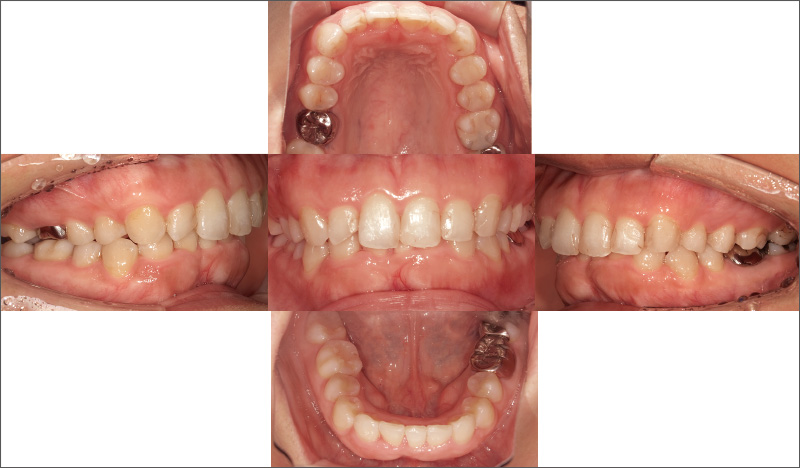

症例1-1 当院にてメインテナンスを行っていた30代女性。口腔内は安定期に入っているが、₂ ₂における審美障害の改善を希望されたため、「iGo」による部分矯正治療を補綴治療前に行い、その後ラミネートべニア修復を行うこととした。 -

症例1-4 15週の治療計画で「iGo」による矯正治療を開始。ラミネートベニアの厚み(1mm)を確保できる位置への歯牙移動を行った。 -